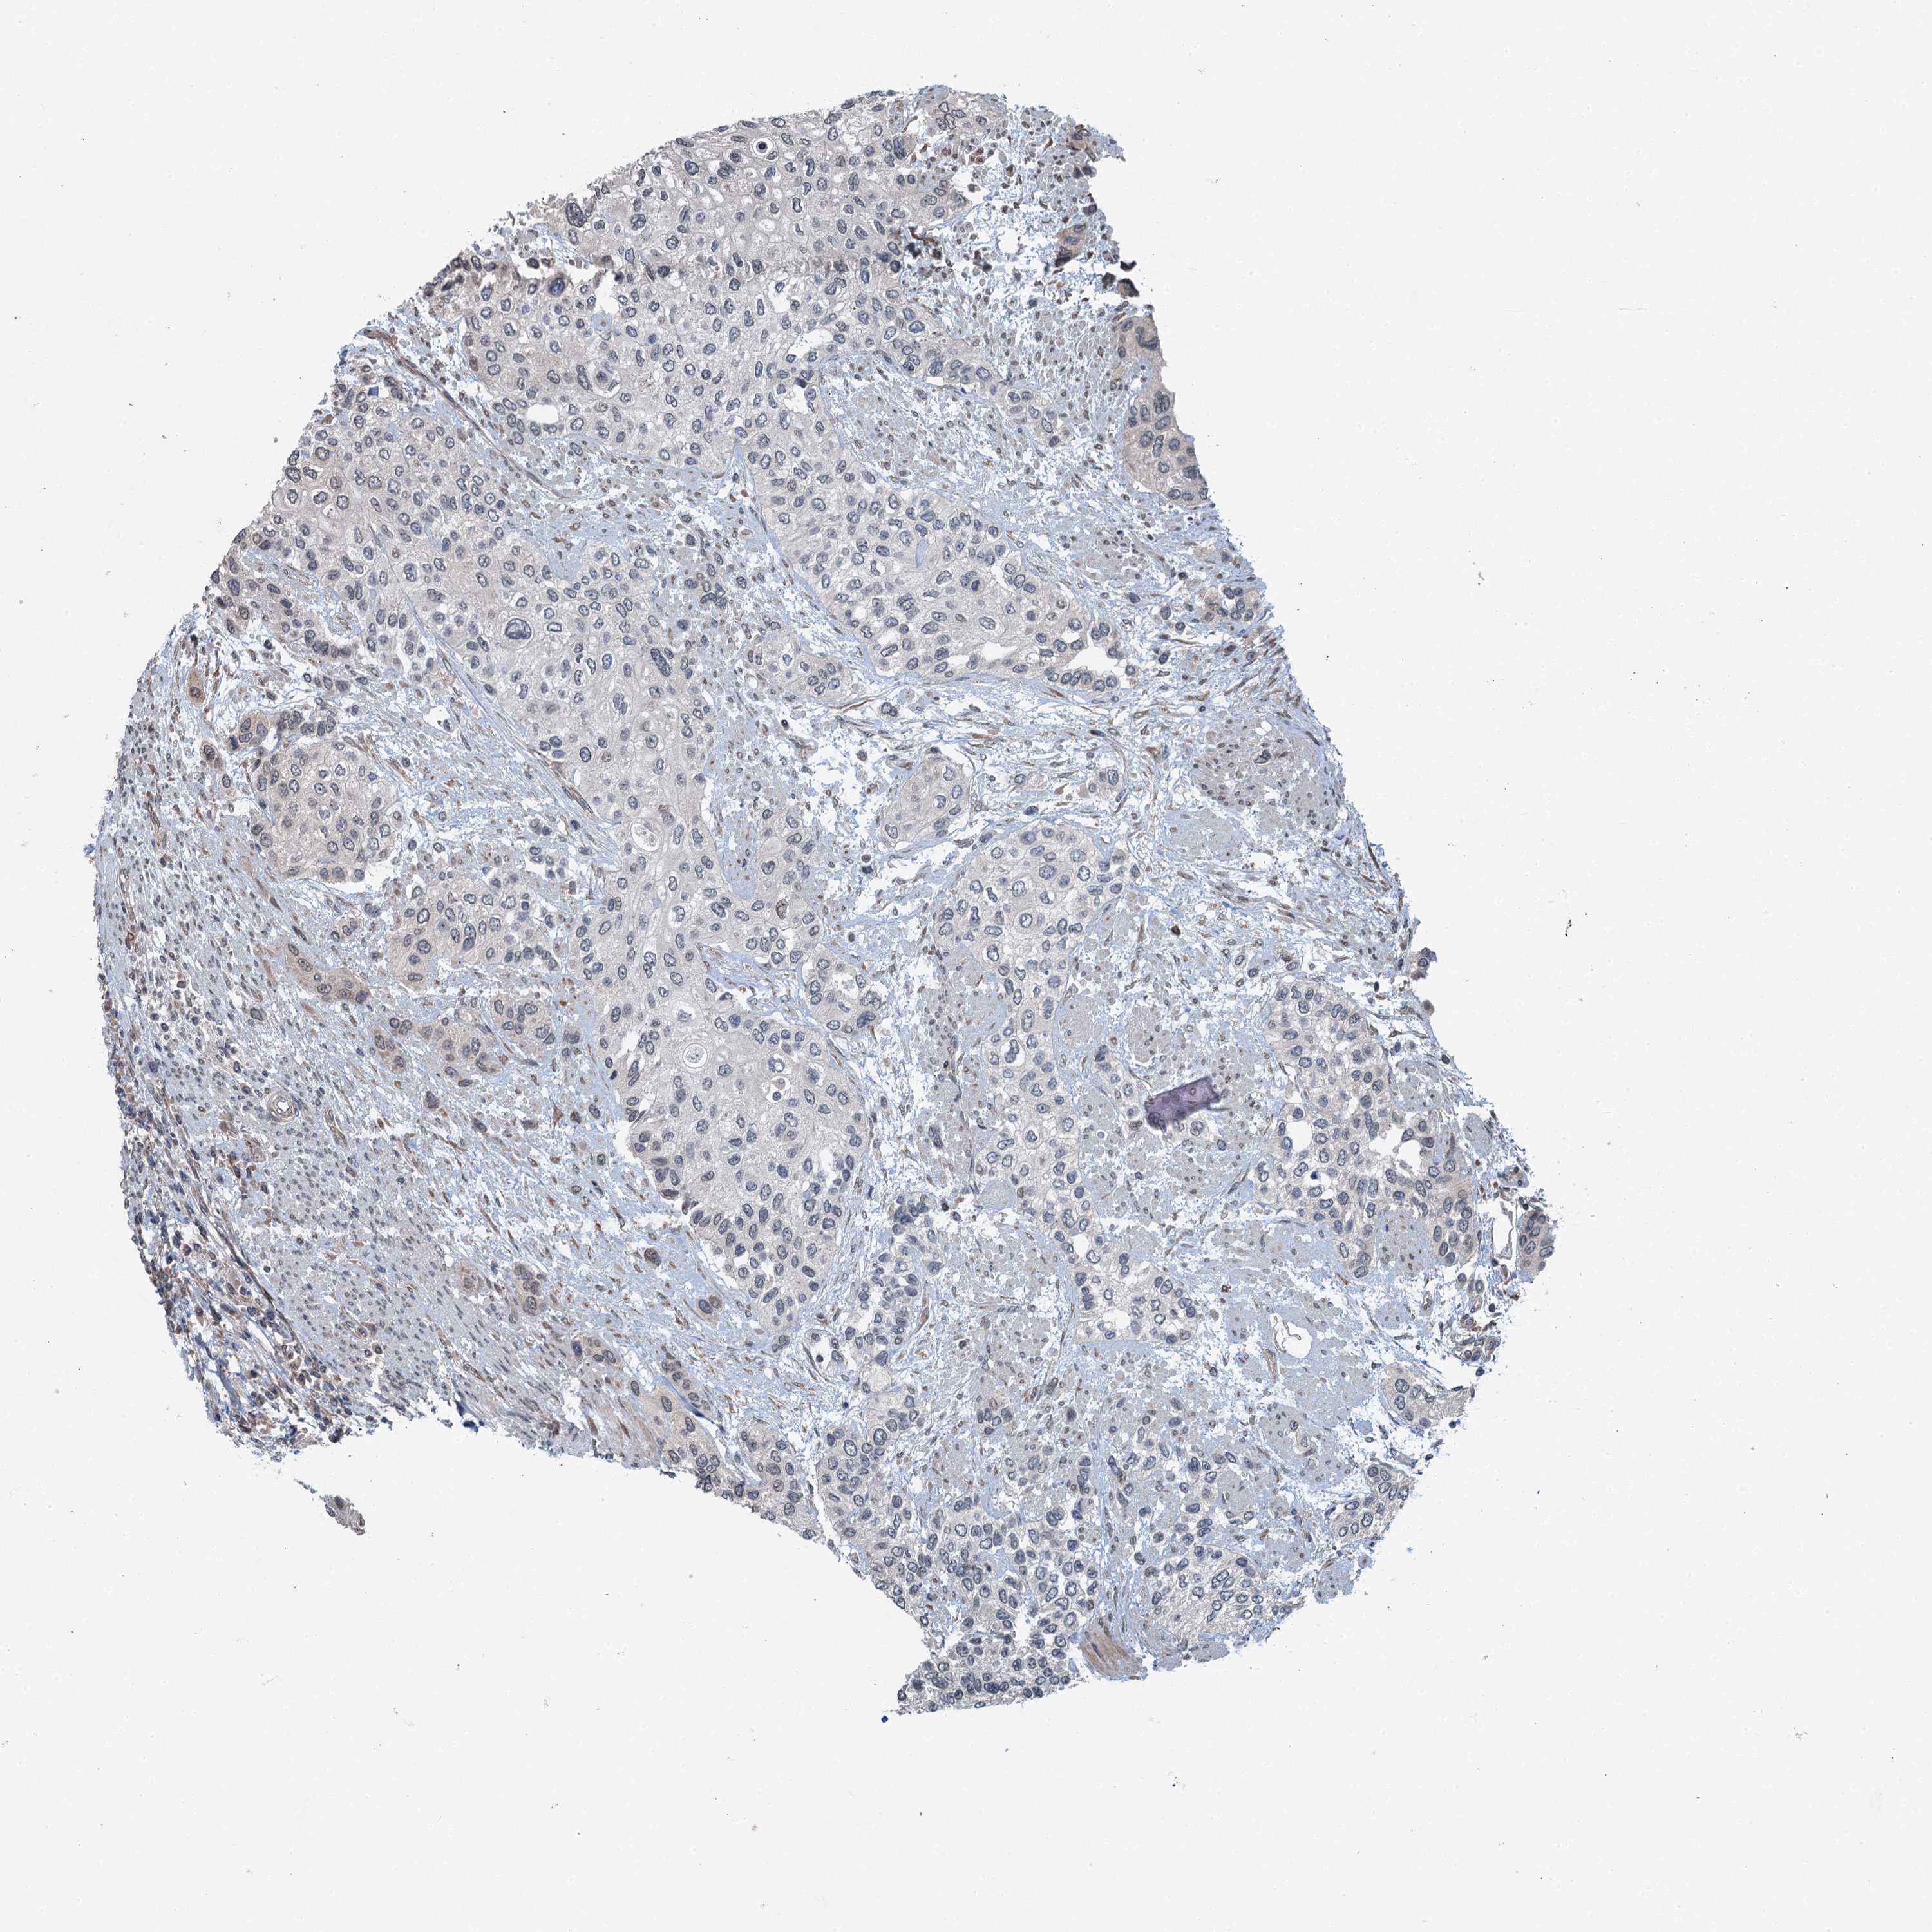

UROTHELIAL CANCER - Protein expressioni

A mouse-over function shows sample information and annotation data. Click on an image to view it in a full screen mode. Samples can be filtered based on level of antibody staining by selecting one or several of the following categories: high, medium, low and not detected. The assay and annotation is described here.

Note that samples used for immunohistochemistry by the Human Protein Atlas do not correspond to samples in the TCGA dataset.

Antibody stainingi

Antibody staining in the annotated cell types in the current human tissue is reported as not detected, low, medium, or high, based on conventional immunohistochemistry profiling in selected tissues. This score is based on the combination of the staining intensity and fraction of stained cells.

Each image is clickable and will lead to virtual microscopy that enables deeper exploration of all samples and also displays staining intensity scores, fraction scores and subcellular localization as well as patient and tissue information for each sample.

Antibody HPA039690

Antibody HPA040231

Staining

High

Medium

Low

Not detected

Intensity

Strong

Moderate

Weak

Negative

Quantity

>75%

75%-25%

<25%

None

Location

Nuclear

Cytoplasmic/membranous

Cytoplasmic/membranous,nuclear

Urothelial carcinoma, High grade

Urothelial carcinoma, Low grade